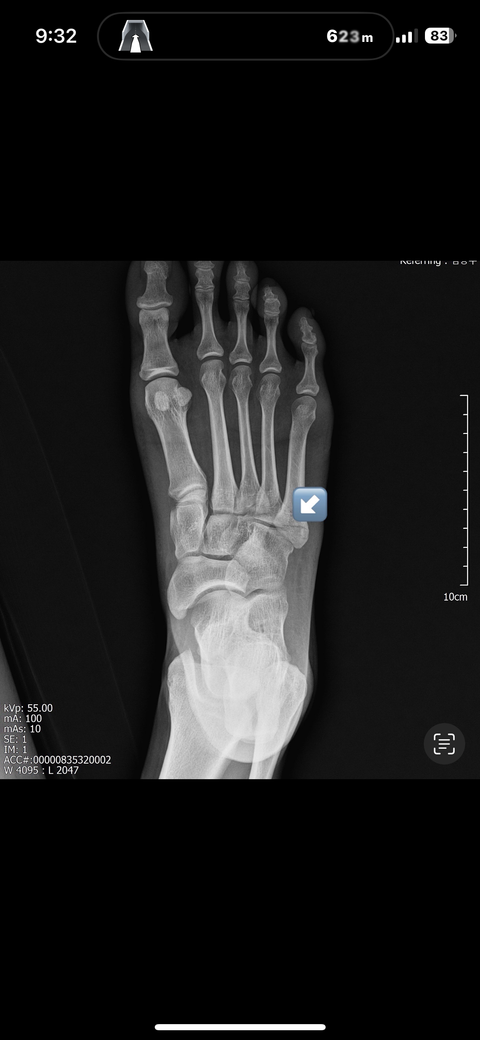

5중족골 골절 수술과비수술 봐주세요

10/5접지름으로인한 5중족골 기저부골절